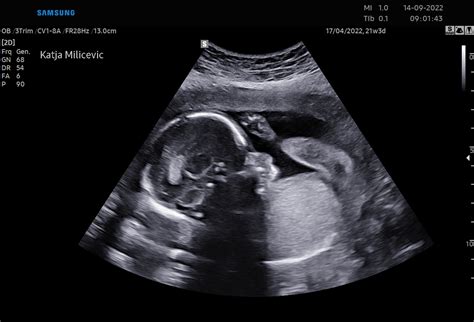

Pregled v tem obdobju običajno traja 15 minut. Izvaja se med 11. in 14. tednom nosečnosti, glede na plodovo dolžino teme-trtica, ki mora znašati med 45 in 84 mm. Praktičen napotek za nosečnico, ki se na pregled naroča na primer po telefonu, je, da pozna prvi dan svoje zadnje menstruacije ali zaprosi za natančno velikost ploda teme-trtica, ki ga izmeri njen ginekolog pri prvem pregledu v nosečnosti. Plodek namreč povprečno zraste 2 mm na dan, zato lahko pri naročanju izberemo najboljši možni čas pregleda.

Preiskavo začnemo z ugotavljanjem števila plodov in zaznavo plodovih utripov. Nato izmerimo natančno dolžino ploda teme-trtica v milimetrih. Velikost mora ustrezati 11. do 14. tednu nosečnosti. Glede na velikost določimo predvideni dan poroda, ki ga kasneje v nosečnosti ne spreminjamo več. Ugotovimo, ali se trajanje nosečnosti ujema z izgubo menstruacije, z dnevom prenosa zarodka pri postopku umetne oploditve, ali pa bo predvideni dan poroda temelji na ultrazvočni meritvi plodove dolžine v primeru, da je do oploditve prišlo v času, ki se ne ujema z datumom zadnje menstruacije.

Glavica in možgani: Izmerimo velikost in ocenimo obliko glavice. Velike nepravilnosti živčevja odkrijemo že v tem času. Nekatere so povezane s kromosomskimi nepravilnostmi, predvsem trisomijo 13 in triploidijo, nekatere pa so posledica nerazvitja lobanjske kosti in so nezdružljive z življenjem. Hrbtenice s hrbtenjačo kot delom živčevja dokončno v tem času še ne moremo oceniti, vendar že lahko ugotovimo večje nepravilnosti ali bolezensko ukrivljenost.

Srce in vratna svetlina: Pri zelo dobrih ultrazvočnih aparatih, ob bogatih izkušnjah zdravnika in ne preveliki telesni teži nosečnice (pri suhih je preglednost boljša) lahko že ocenimo osnovno sestavo srca - štiri votline in izstopišča dveh velikih žil. Vendar natančneje srca v tem času še ne preiskujemo. Ocenimo le utrip srca v minuti, saj so nekatere kromosomske nepravilnosti povezane s prevelikim ali premajhnim srčnim utripom. Ultrazvočno je moč zaznati plodov utrip že pri 5 tednih in pol. Ob dodatnih opozorilnih znakih, na primer povečani vratni svetlini več kot 3,5 mm, odsotnosti nosne kosti ali bolezenskem pretoku v plodovem žilju, natančno preiščemo plodovo srce okoli 20. tedna nosečnosti, skupaj s pediatrom kardiologom, ki je za pregled plodovega srca posebej izkušen. Dokazano je, da je izmerjena povečana vratna svetlina dober napovedni dejavnik ne le za kromosomsko nepravilnost ploda, temveč tudi za ugotavljanje srčne napake tako pri zdravih kot kromosomsko drugačnih zarodkih.

Želodec in mehur: V trebuščku poiščemo želodec, ki leži pod in na isti strani kot srce. V tem času plod že požira plodovnico. Želodec se tako razpira in posredno ocenimo, ali so se prebavila pravilno razvila in ali ležijo v trebušni votlini. Ogledamo si obliko trebušne stene glede na prsno steno. Pod želodcem natančno pogledamo, ali je vstopišče popkovnice v trebušček zaprto. Odprta trebušna stena je običajno znak kromosomske nepravilnosti 18. ali 13. kromosoma ali triploidije. Pri pregledu spodnjega dela trebuha najdemo plodov mehur. Ocenimo njegovo prisotnost ter velikost. Četrtina kromosomsko drugačnih plodov ima namreč zmerno povečan mehur.

Roke in noge: Nato preiščemo plodove roke in noge. Dolžine kosti ne merimo, le kot zanimivost naj povemo, da so dolge okrog 12 mm in da je dolžina stopala približno enaka dolžini stegnenice. Ogledamo si lego udov ter gibanje zarodka.